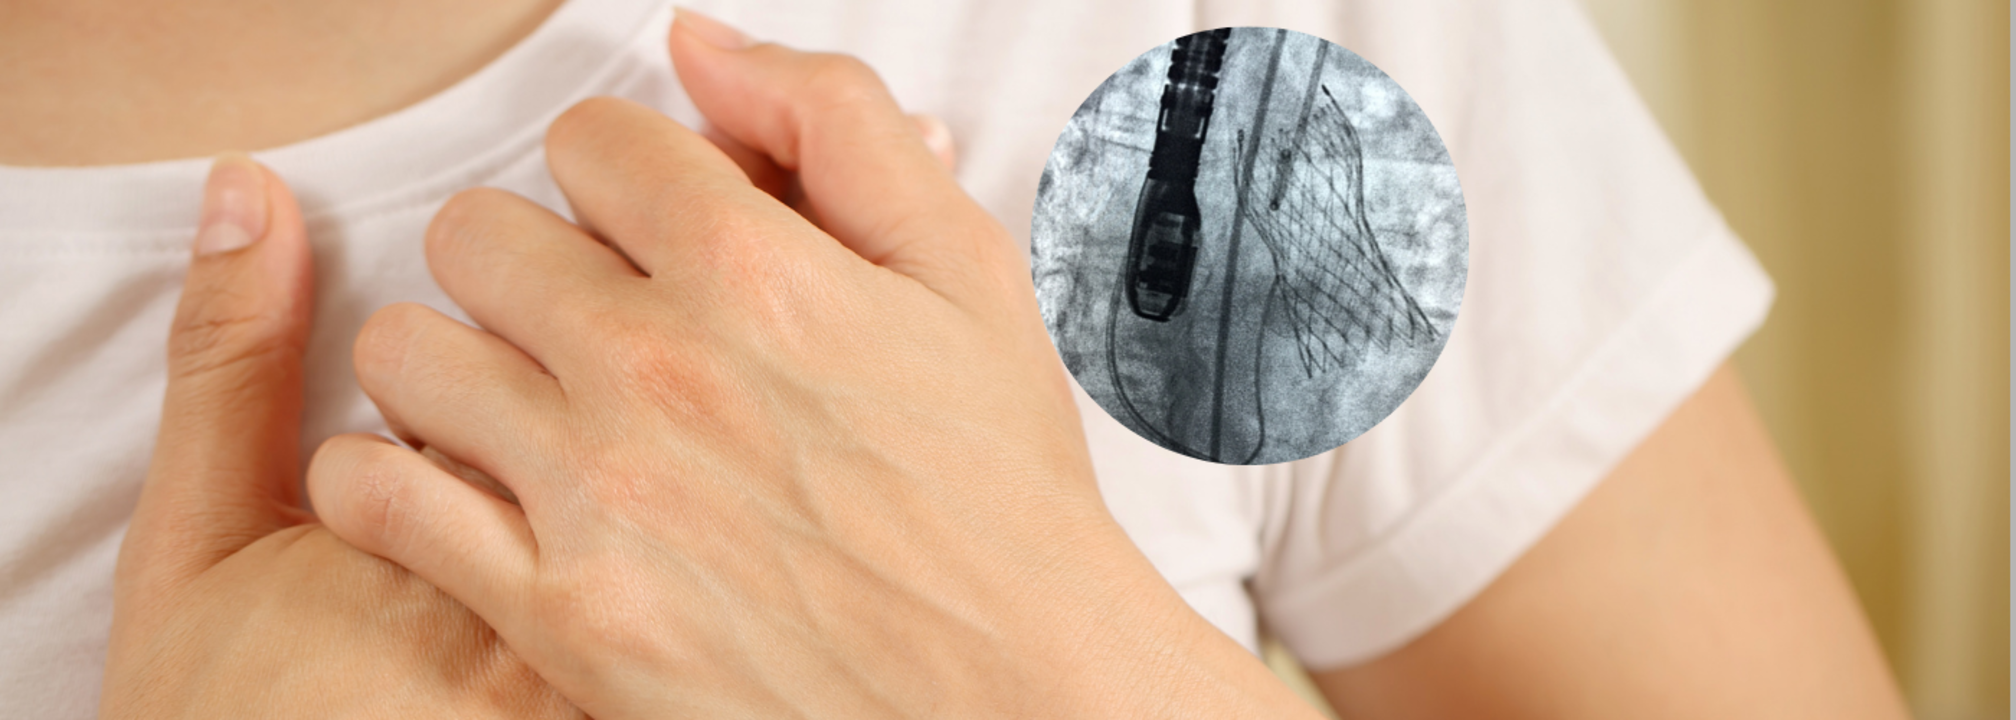

Heart disease or cardiovascular conditions still stand at the top of the causes of death all over the world. Innovations in medical technology give hope and solutions to the patients. The most promising innovation in heart valve disease treatment is 'Transcatheter Aortic Valve Implantation'.The Rise of TAVI TechnologyAortic stenosis is a condition where the aortic valve in the heart becomes narrowed, which prevents the free flow of blood. Traditionally, it has been treated by open-heart procedure, which entails a considerable recovery period. The risks of this procedure are often intimidating for elderly patients or those with other health conditions. TAVI has been changing very fast. What used to be a treatment option for patients at high risk is now being used for more individuals, including those at intermediate and low risk. It has been mainly because of the continued evolution in the technologies of the device, the techniques of the procedure, and the criteria of the patients, which makes TAVI accessible and safer for many.The Role of Innovation in TAVITechnological innovations have been at the heart of TAVI. Early models were huge in size and sometimes awkward to negotiate into place. The engineers have conducted a lot of work in producing smaller valves made of better elastomers, such as those from bovine pericardium that envelops the heart and polymer mesh. These newer devices are easier to implant, offer improved durability, and cause less trauma to the surrounding arteries and tissues.Apart from device innovations, advances in imaging technology have dramatically increased the accuracy of TAVI procedures. High-resolution 3D imaging, including CT scans, allows cardiologists to map the vascular system and the heart in a patient and thus accurately size and position the valve. This means reduced complications, improved outcomes, and an increase in overall success rates.With this said, the future of TAVI is promising in its innovative developments that can deliver much success and even fewer complications. Indeed, such an advancement can include developing next-generation valves more robust and durable in resistance to long-term wear and tear. Other trends with interest in this realm are the growing demand in TAVI procedures with incorporating AI for enhanced planning before the procedure and predictive analytics in real-time during monitoring.With advancements in technology and deeper clinical understanding, the future for TAVI is very bright because more opportunities for improving heart health will be unlocked. Thus, the patient is exposed to a safer, quicker, and more effective alternative option than traditional procedure. Definitely, with the future of heart health in mind, TAVI is certainly one of the most promising innovations in modern cardiology.